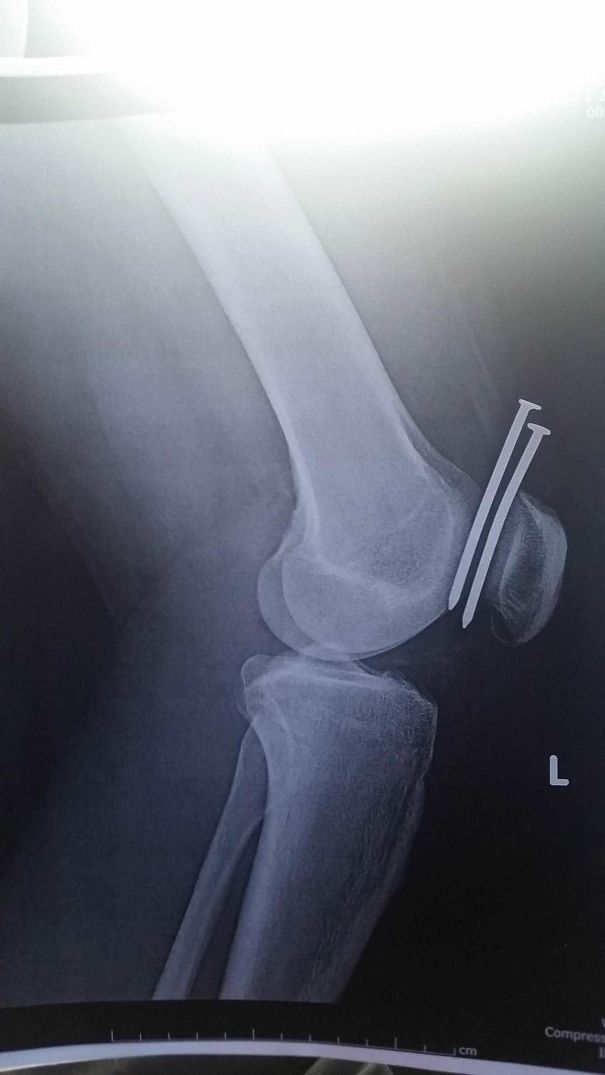

This Guy Had Two Nails From A Nail Gun Hit His Leg, And They Both Missed His Femur And His Kneecap